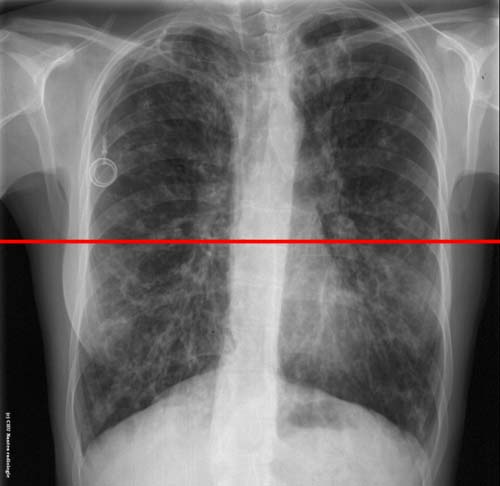

DDB : niveau de la coupe TDM